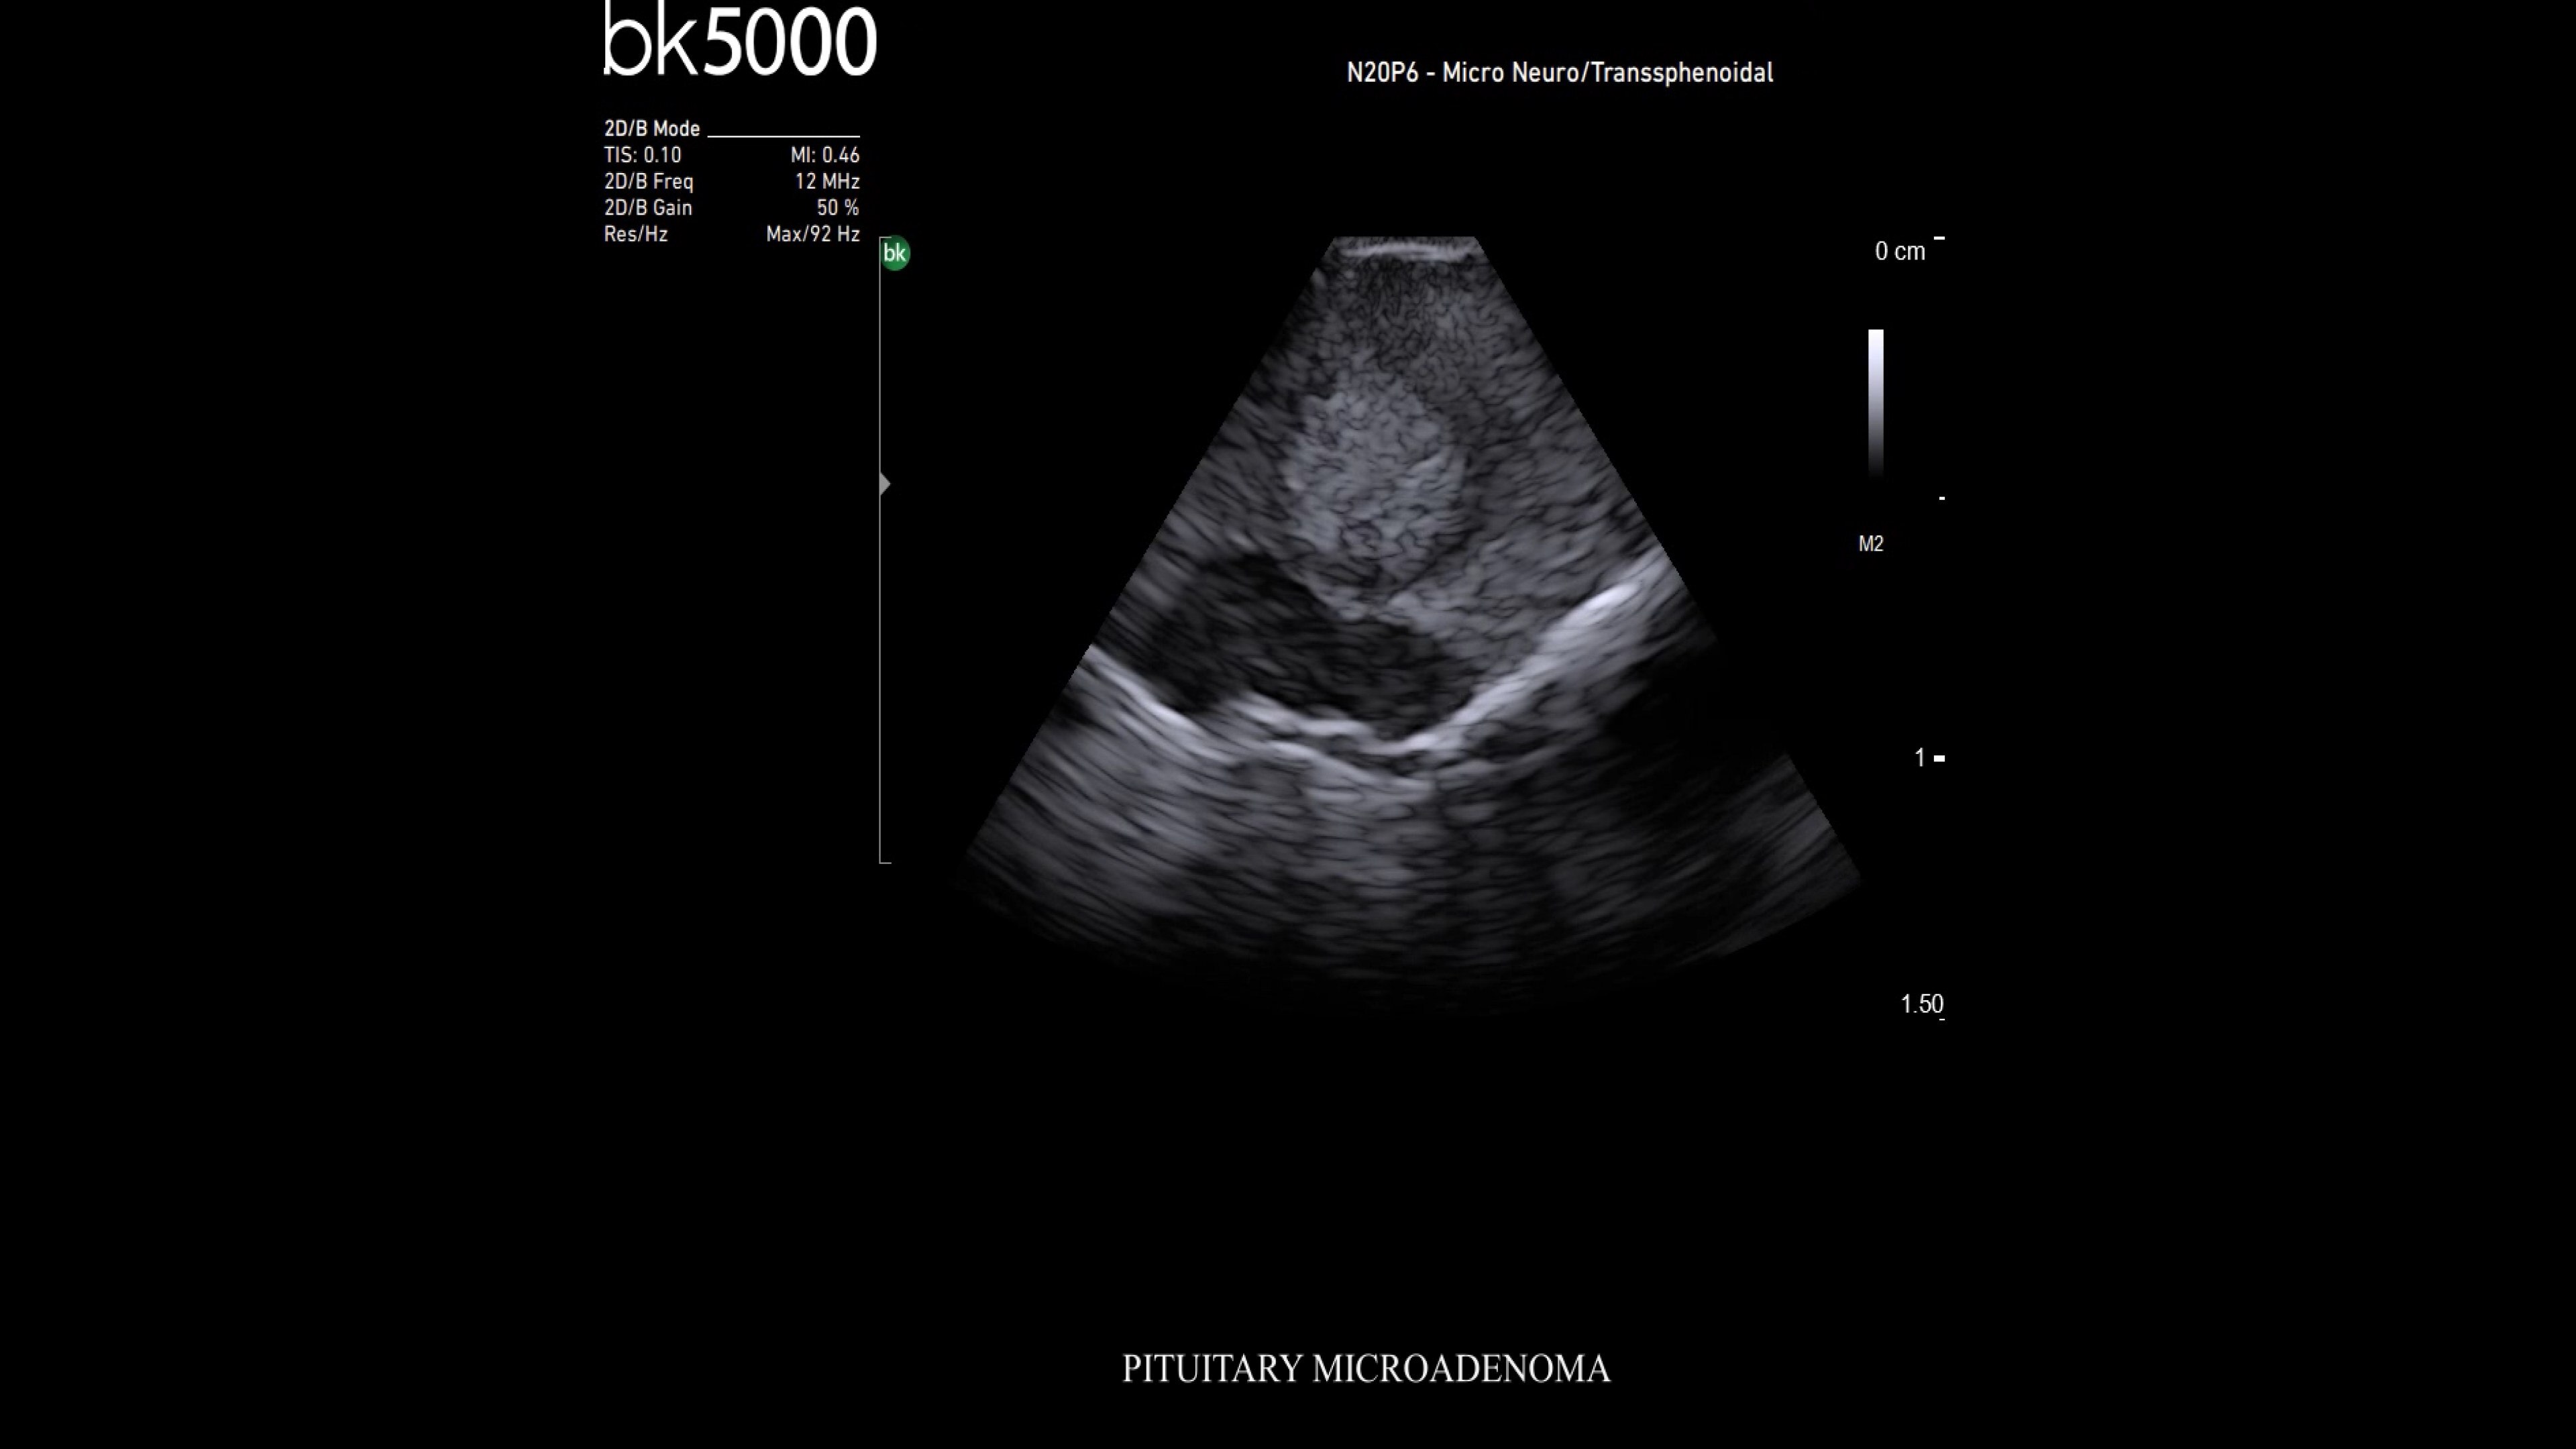

Ultrasound enhances neurosurgery by providing real-time navigation and lesion identification, crucial as preoperative CT/MRI data can be outdated. The bk5000 system offers high-quality images to see lesion margins and determine actions. Advanced graphics processing ensures immediate, auto-optimized images.

• Neurosurgery transducers: High-resolution, sterilizable transducers provide detailed brain and spinal cord images. The Smart™ button allows easy activation, freezing, storing, or printing of images. Disposable needle guides aid lesion targeting.